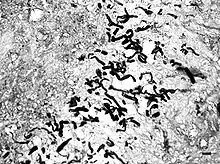

Pythiosis is caused by Pythium insidiosum and occurs most commonly in dogs and horses, but is also found in cats, cattle, and humans. In the United States it is most commonly found in the Gulf states, especially Louisiana, but has been found in midwest and eastern states. It is also found in southeast Asia, eastern Australia, New Zealand, and South America. Pythiosis occurs in areas with mild winters due to the organism surviving in standing water that does not reach freezing temperatures.[2] Pythium occupies swamps in late summer and infects dogs who drink water containing it. The disease is typically found in young, large breed dogs.[1]

It is suspected that pythiosis is caused by invasion of the organism into wounds, either in the skin or in the gastrointestinal tract.[2] The disease grows slowly in the stomach and small intestine, eventually forming large lumps of granulation tissue. It can also invade surrounding lymph nodes. Symptoms include vomiting, diarrhea, depression, weight loss, and a mass in the abdomen. Pythiosis of the skin in dogs is very rare, and appears as ulcerated lumps. Primary infection can also occur in the bones and lungs.

In horses, subcutaneous pythiosis is the most common form and infection occurs through a wound while standing in water containing the pathogen.[3] The disease is also known as leeches, swamp cancer, and bursatti. Lesions are most commonly found on the lower limbs, abdomen, chest, and genitals. They are granulomatous and itchy, and may be ulcerated or fistulated. The lesions often contain yellow, firm masses of dead tissue known as kunkers.[4] It is possible with chronic infection for the disease to spread to underlying bone.[5]